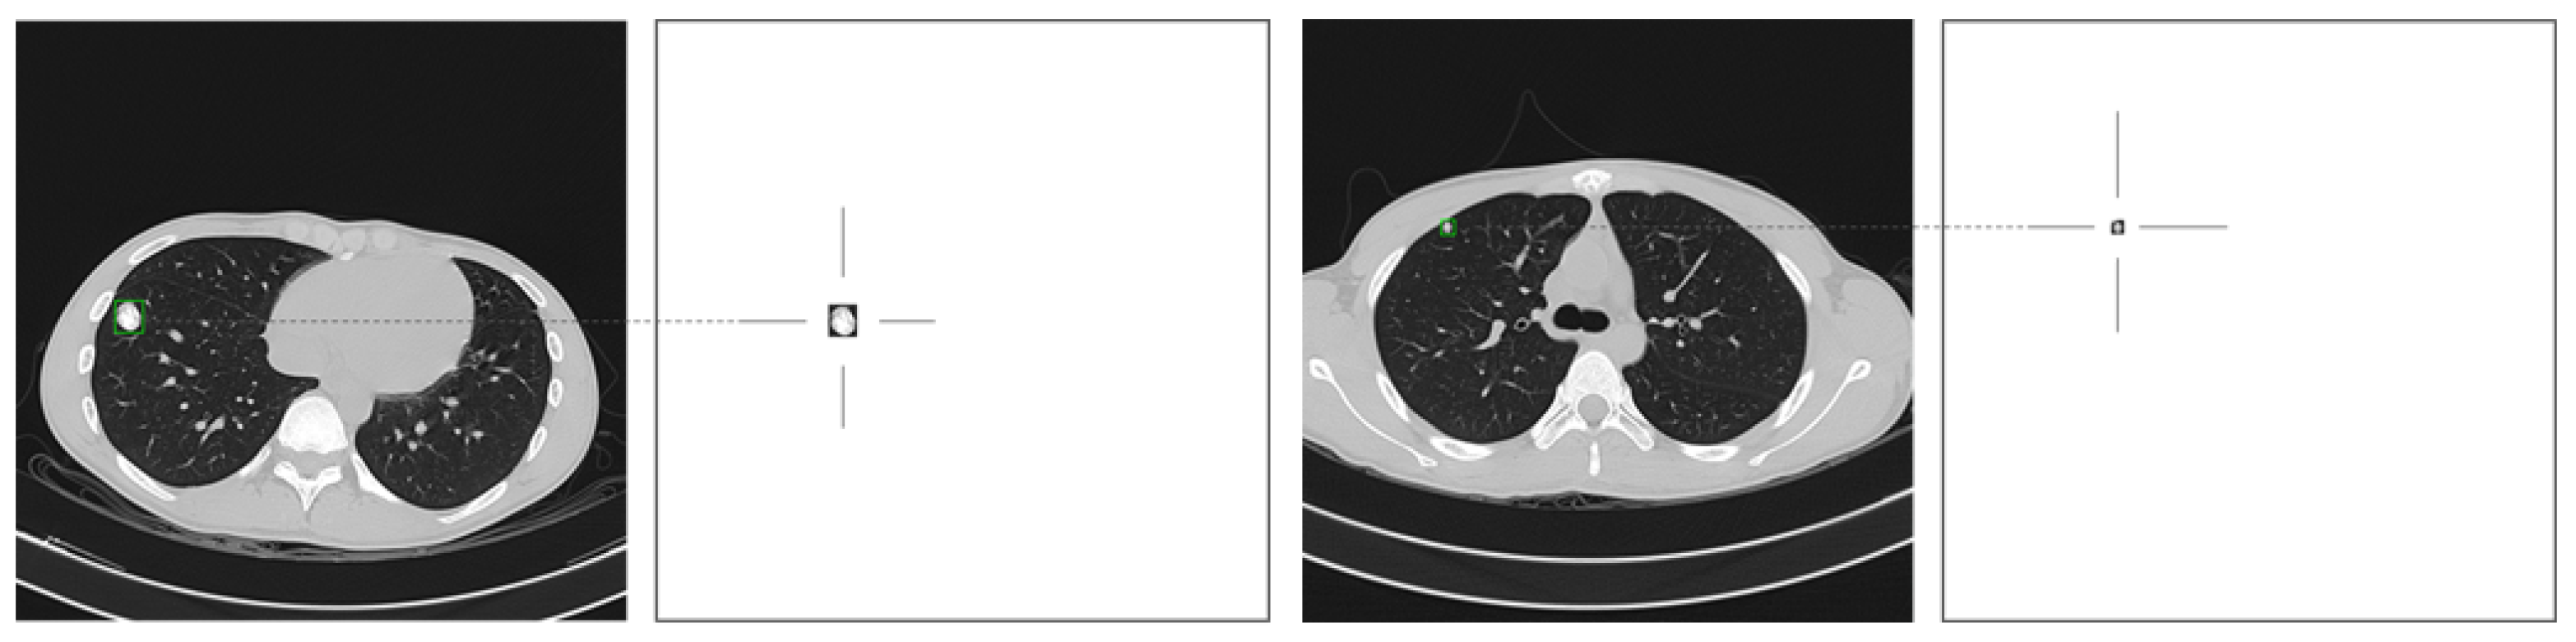

2.1.2. Ground Truth

2.1.3. Datasets